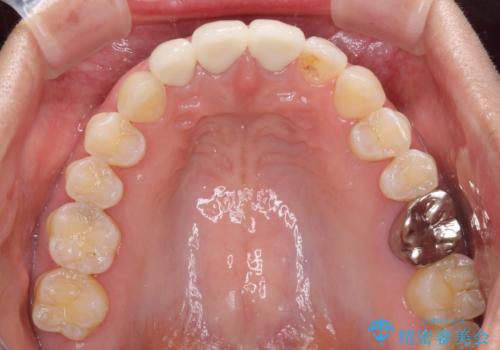

前歯は一部根管治療を行った後にオールセラミッククラウンに補綴することとしました。

補綴治療に先立ち、下顎前歯の部分矯正を行い、前歯の咬み合わせの安定性向上を図りました。

当初は上顎の補綴治療のみを希望されていましたが、仮歯装着期間に上下の前歯の接触が気になったため、部分矯正を行うこととしました。